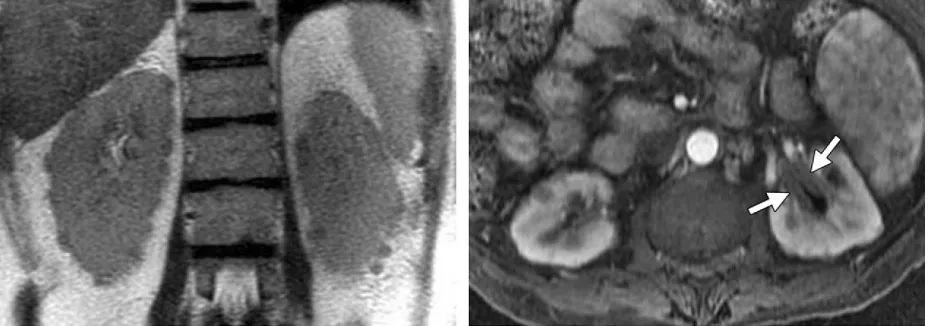

MRI 表现

女,63 岁。胰腺外分泌功能降低,B 超检查发现胰头增大

肾脏受累

肾脏受累治疗后